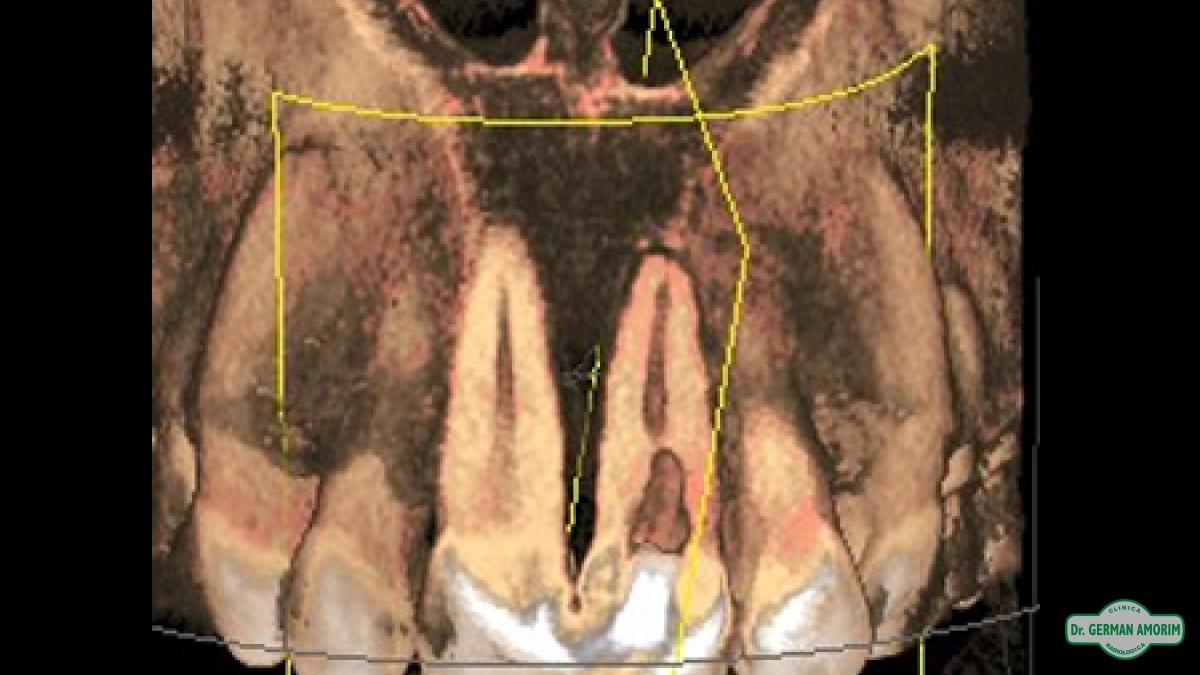

La radiografía tridimensional también tiene mucha utilidad de en Endodoncia como se ve en este caso que detallamos a continuación.

El profesional no podía encontrar el conducto en la radiografía periapical estándar. Al ser bidimensional no lo veía y por eso le indicó una tomografía volumétrica digital (TVD).

En la imagen tridimensional se pudo apreciar dónde estaba el conducto . Como se ve en las imágenes tridimensionales faltó muy poco para hacer una perforación ya que el profesional se estaba yendo hacia vestibular. Gracias a la TVD se pudo identificar y hacer el tratamiento de endodoncia sin problemas.